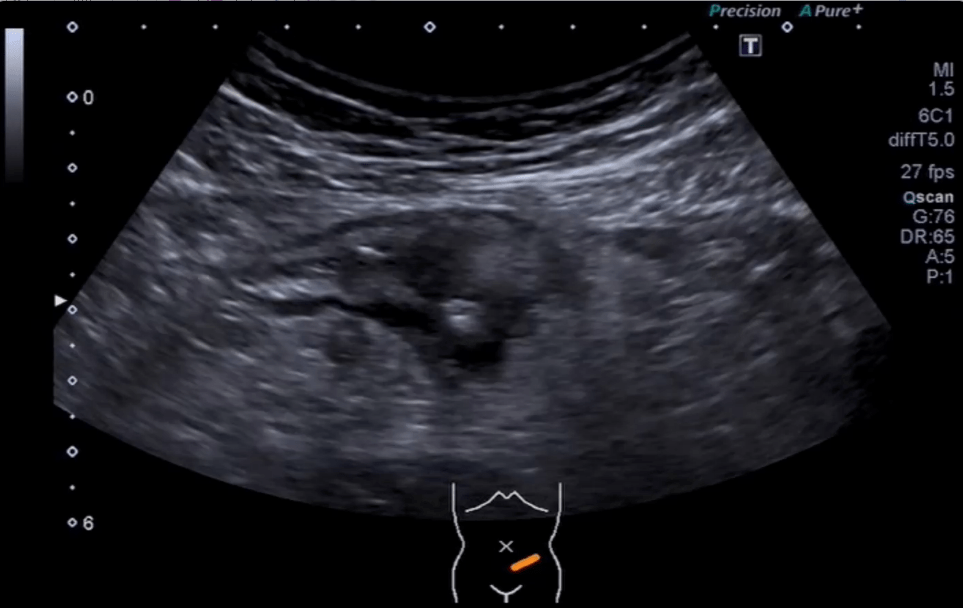

Ultrasound showed splenomegaly and a solid mass tumor: a large hypoechoic focal lesion located near the splenic hillum Further assesment with contrast enhanced ultrasound revealed a rapid influx of the contrast agent, resulting in enhancement in the arterial phase, non-enhancing in the middle and intense wash-out in late phases.

Splenectomy was performed and histopathological examination confirmed the diagnosis of splenic Burkitt lymphoma.